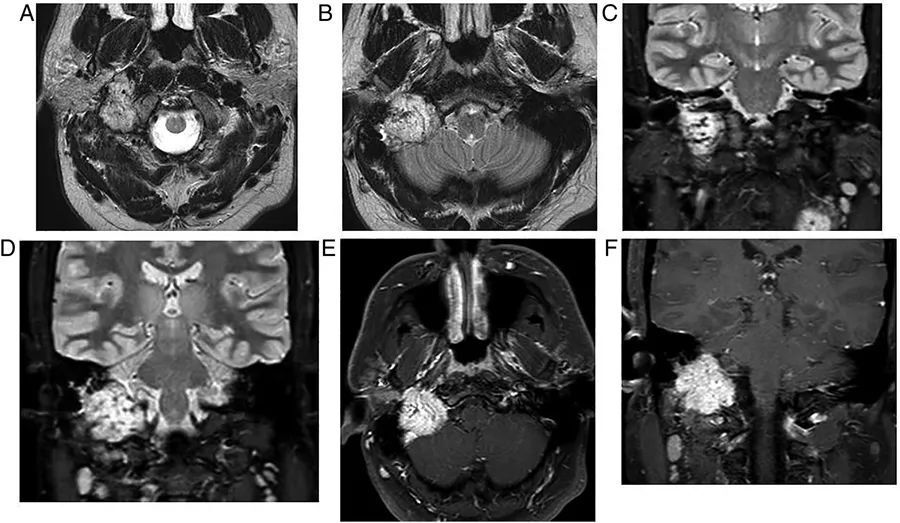

图4  巨大椎基底动脉连接处动脉瘤。患者表现为延髓症状,影像学显示左侧桥小脑角区不规则占位性病变,并呈流空信号,第四脑室受压变形,通过血管造影最终证实了巨大动脉瘤的诊断

图5  右侧桥小脑角区脑膜瘤。可见类圆形病灶压迫右三叉神经和脑桥,增强扫描可见显著均匀强化,强化的硬脑膜尾沿着颞骨岩部向下延伸

图6  左侧桥小脑角区表皮样囊肿。病灶呈T1低信号、T2高信号,DWI上弥散受限,延伸至Meckel氏腔,左侧小脑中脚和第四脑室受压,三叉神经、面神经、听神经也被压缩

图7  蛛网膜囊肿。可见右侧桥小脑角区呈脑脊液信号的不规则肿物,右侧小脑半球受压变形

图8  双侧桥小脑角区脂肪瘤。T1WI上呈现高信号,压脂像上则无信号。如果只根据增强扫描的图像(E和F),很容易将脂肪瘤误认为前庭神经鞘瘤或脑膜瘤